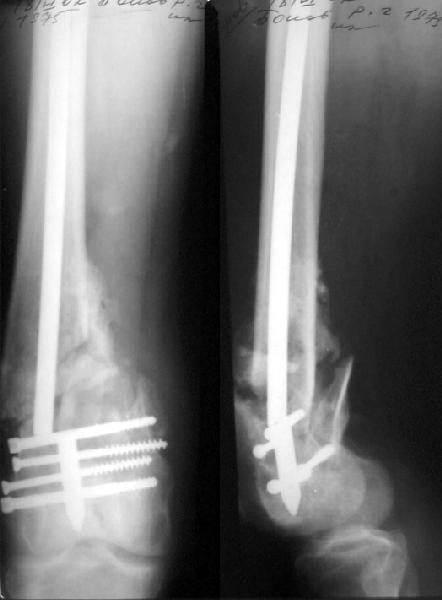

Пациент 27 лет оперирован 2.04.02 через 2 недели после открытого перелома дистального отдела бедренной кости (1 снимок).

Сделан антеградный закрытый интрамедуллярный остеосинтез UFN 11 мм (2 снимок). Вторая нога была ампутирована по месту первичного поступления. Для возможности ранней нагрузки использованы блокирующие винты 6 мм, для чего дистальные отверстия были рассверлены. К двум месяцам начал вставать на костыли, до того занимался разработкой движений в колене. Эти циклические движения в сочетании с тем, что зона концентрации нагрузок приходилась как раз на уровень отверстия, и что перелом открытый и тяжелый и не успел прочно схватиться, привели к перелому стержня 8 июня (3 снимок). Вчера госпитализировали. Такое осложнение у нас впервые. Пока думаем про реостесинтез - вытолкнуть дистальный отломок через дистально, да и через то же отверстие заштифтовать ретроградно. Илиналожить аппарат после удаления центрального отломка стержня, если что-то не будет получаться. Или подумать про пластинку?Заранее спасибо.